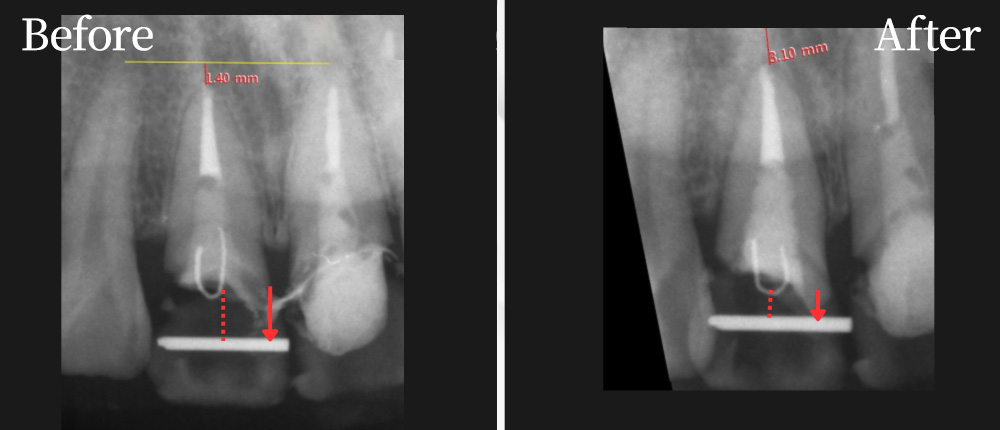

前歯が破折し、十分なフェルールが確認確保できない症例

マイクロスコープで破折線の位置を確認し、動揺などを診ながら2〜6ヶ月かけて挺出固定。

上の図のように歯根にワイヤーを埋め込み、仮歯にもあるワイヤーとゴムで連結し引っ張る。

その後、必要に応じて歯肉の形を整えながら、歯冠修復が可能。